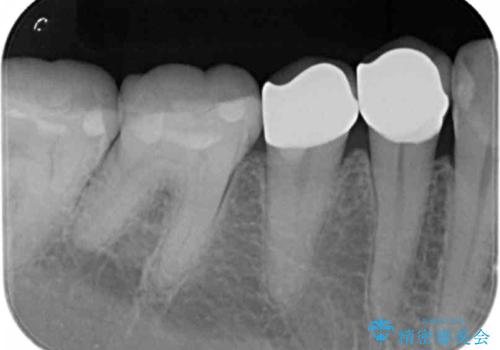

- 右下45:仮歯+ジルコニアクラウン/11,000円+110,000円費用は治療当時の料金となります

度重なる治療で継ぎ接ぎになってしまった場合はクラウンで歯を覆った方が虫歯・着色のリスクを減らすことができます。